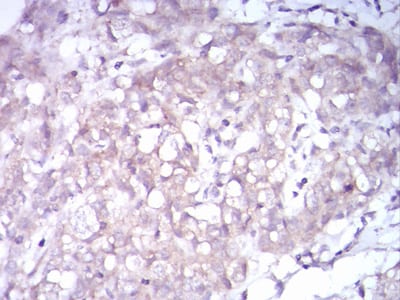

分类: 科研抗体货号: 30883别名: TRKB; trk-B; GP145-TrkB应用: IHC反应种属: Human